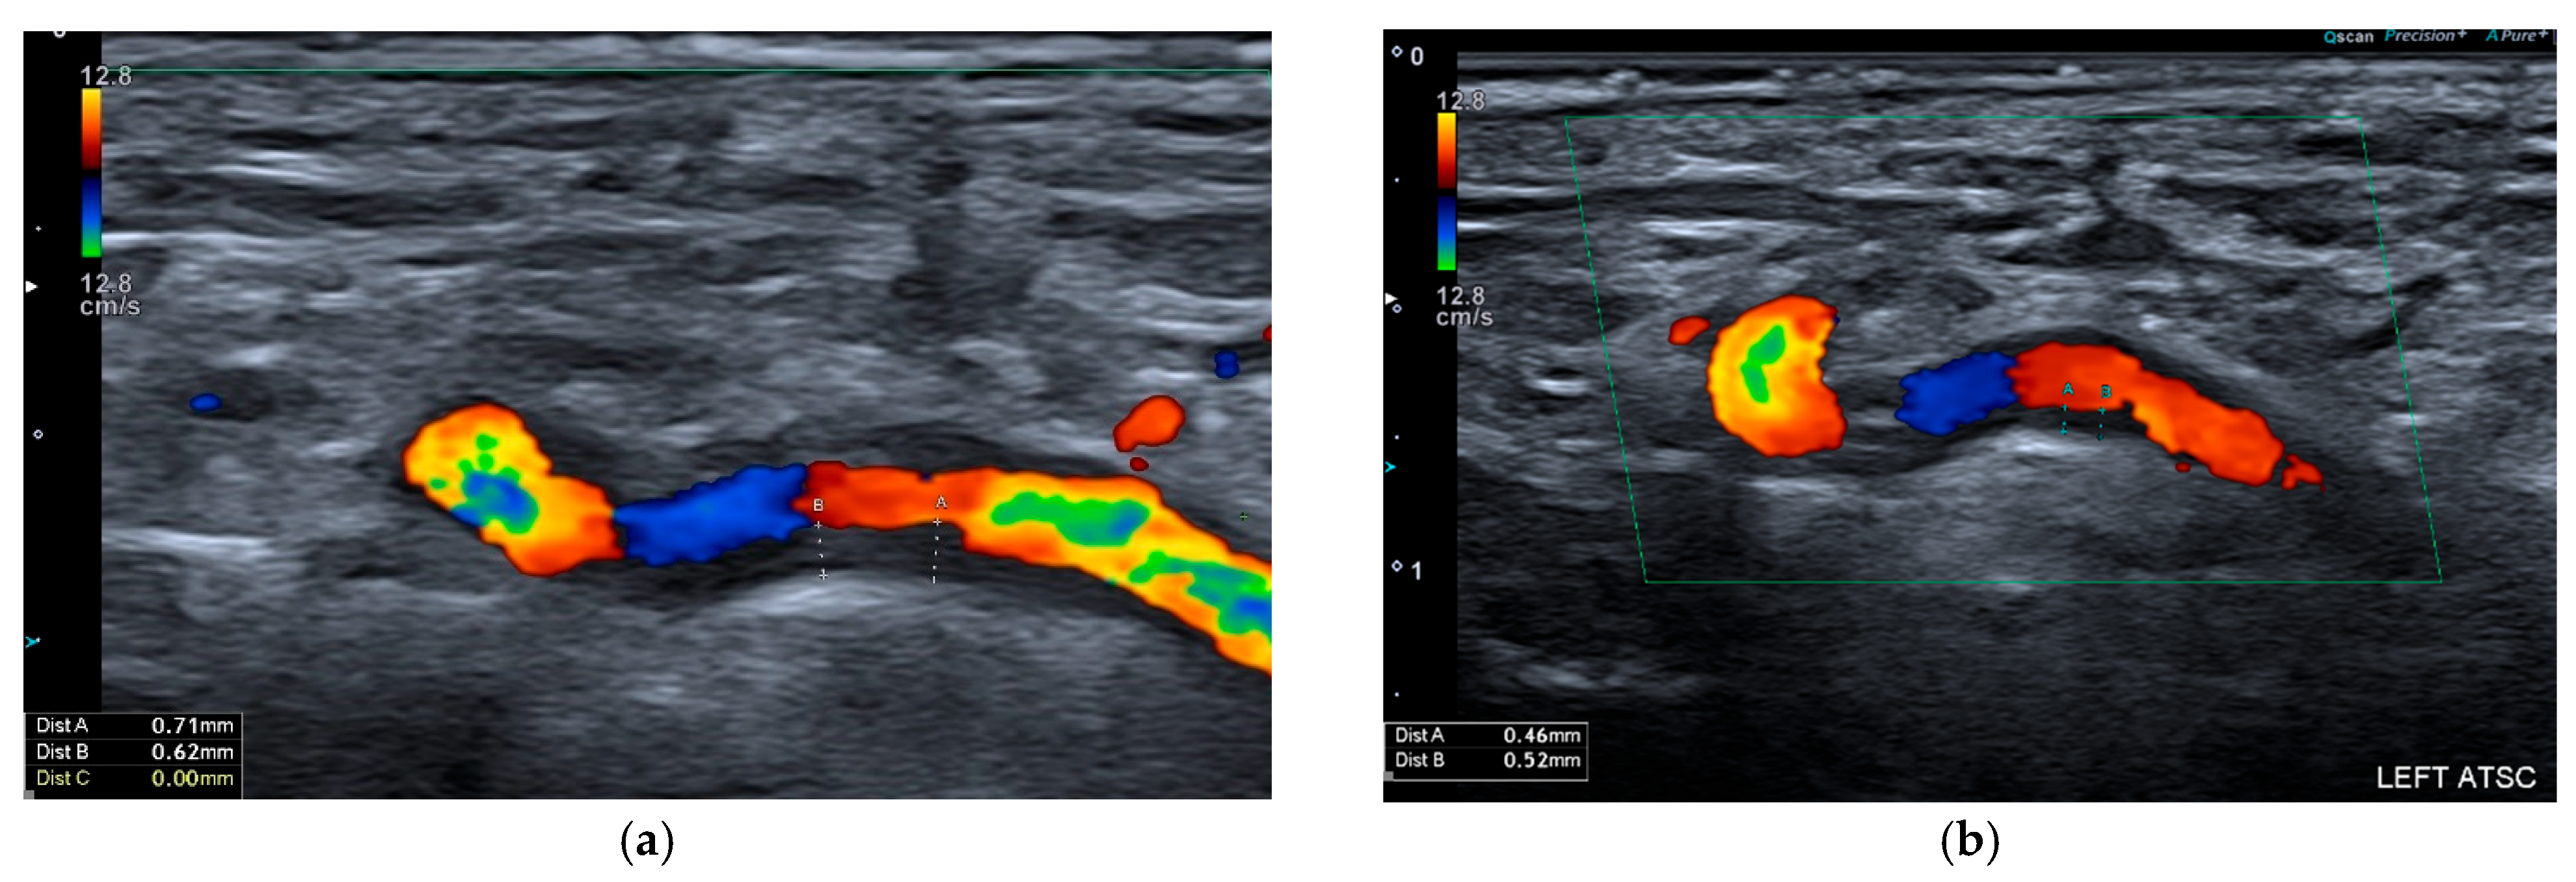

2. Ultrasound

2.1. Giant Cell Arteritis

2.2. Takayasu Arteritis